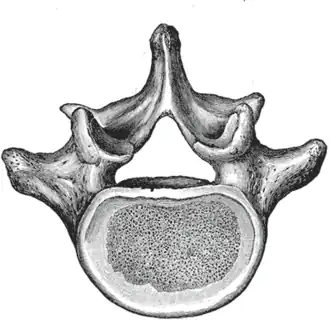

Kenmerkend voor lendenwervels is dat zij, in vergelijking met de andere wervels, het grootste wervellichaam (lat.: corpus vertebrae) hebben. Tevens is het doornuitsteeksel (lat.: processus spinosus) erg groot in vergelijking met de andere wervels, en wijst het recht naar achteren. De gewrichtsuitsteeksels (lat.: processus articularis) hebben een oriëntatie in het zijwaartse vlak, waardoor er in dit deel van de wervelkolom voornamelijk voor/achterwaartse bewegingen plaats kunnen vinden.